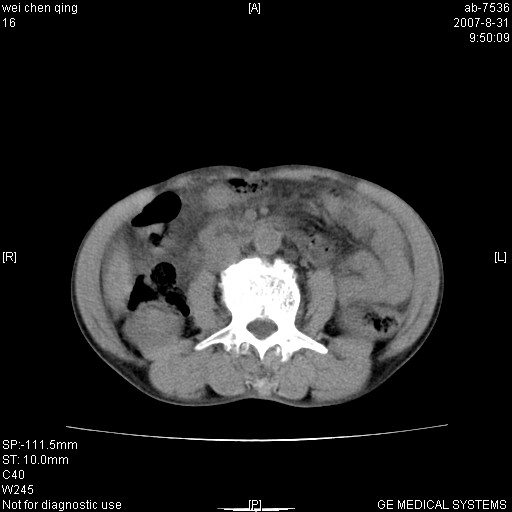

以下是引用zyyzzy在2007-8-31 14:34:00的发言:[br]该病人肝内胆管扩张,胆囊及胆总管未见明显扩张。在倒数第9层图像上可看到左右肝管结合部(肝总管)有软组织影,此处应薄层扫描。考虑肝总管占位(ca)、腹水。[br]